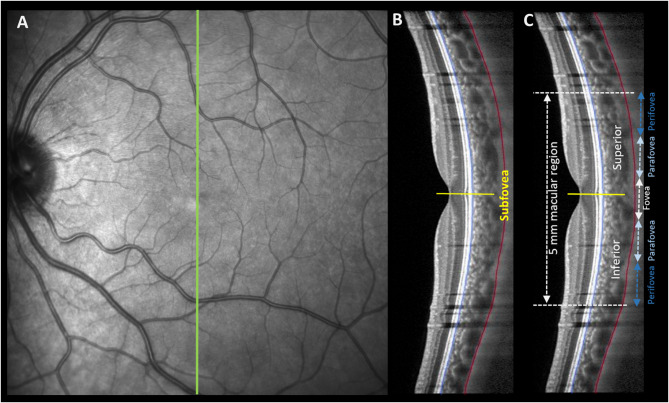

Results: Compared with sham control (2 ± 1 μm, n = 20) and red light (-1 ± 2 μm, n = 6) stimulation, subfoveal choroidal thickness increased within 60 min after blue light stimulation of the blind spot (7 ± 1 μm, n = 20; main effect of light, p < 0.001). Significant choroidal thickening after blue light stimulation occurred in emmetropes (10 ± 2 μm, p < 0.001) but not in myopes (4 ± 2 μm, p > 0.05). Choroidal thickening after blue light stimulation was greater in the fovea, diminishing in the parafoveal and perifoveal regions. There was no significant main effect of light, or light by refractive error interaction on the axial length after blind spot stimulation.